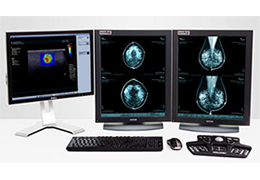

单屏工作效率与安全

ImageView 软件平台旨在通过提供以下功能,大幅提高影像效率和安全性:

所有 Carestream 影像采集产品通用的用户界面

减少屏幕切换,节省时间并增强工作流程